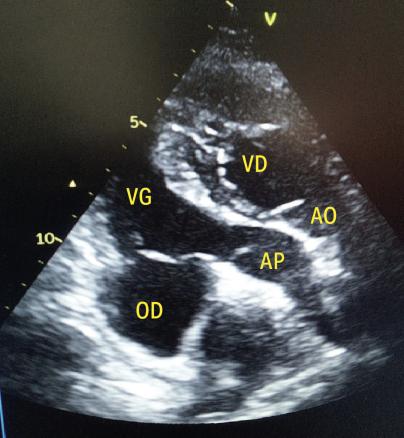

Un homme de 39 ans consulte pour une dyspnée d’effort apparue progressivement et des palpitations intermittentes. L’examen clinique est normal. L’électrocardiogramme montre un PR allongé. L’échocardiographie transthoracique révèle une discordance atrioventriculaire et ventriculo‑artérielle, compatible avec une transposition des gros vaisseaux congénitalement corrigée : l’aorte naît du ventricule droit morphologique, tandis que l’artère pulmonaire émerge du ventricule gauche morphologique, suivant un trajet parallèle (figure). Du fait de l’absence d’anomalies valvulaires associées, un traitement médical symptomatique est instauré, avec une bonne évolution.

La transposition des gros vaisseaux congénitalement corrigée (L‑TGV) est une cardiopathie congénitale rare (environ 0,5  % des malformations) caractérisée par une correction physiologique de la circulation malgré des connexions cardiaques inversées. Le diagnostic est souvent tardif, à l’âge adulte, révélé par une dyspnée, des palpitations ou des troubles conductifs, notamment un bloc atrioventriculaire progressif.1 Le pronostic dépend de la fonction du ventricule et de la valve auriculoventriculaire systémiques (ventricule droit morphologique).

L’échocardiographie complétée par une imagerie par résonance magnétique cardiaque pose le diagnostic.